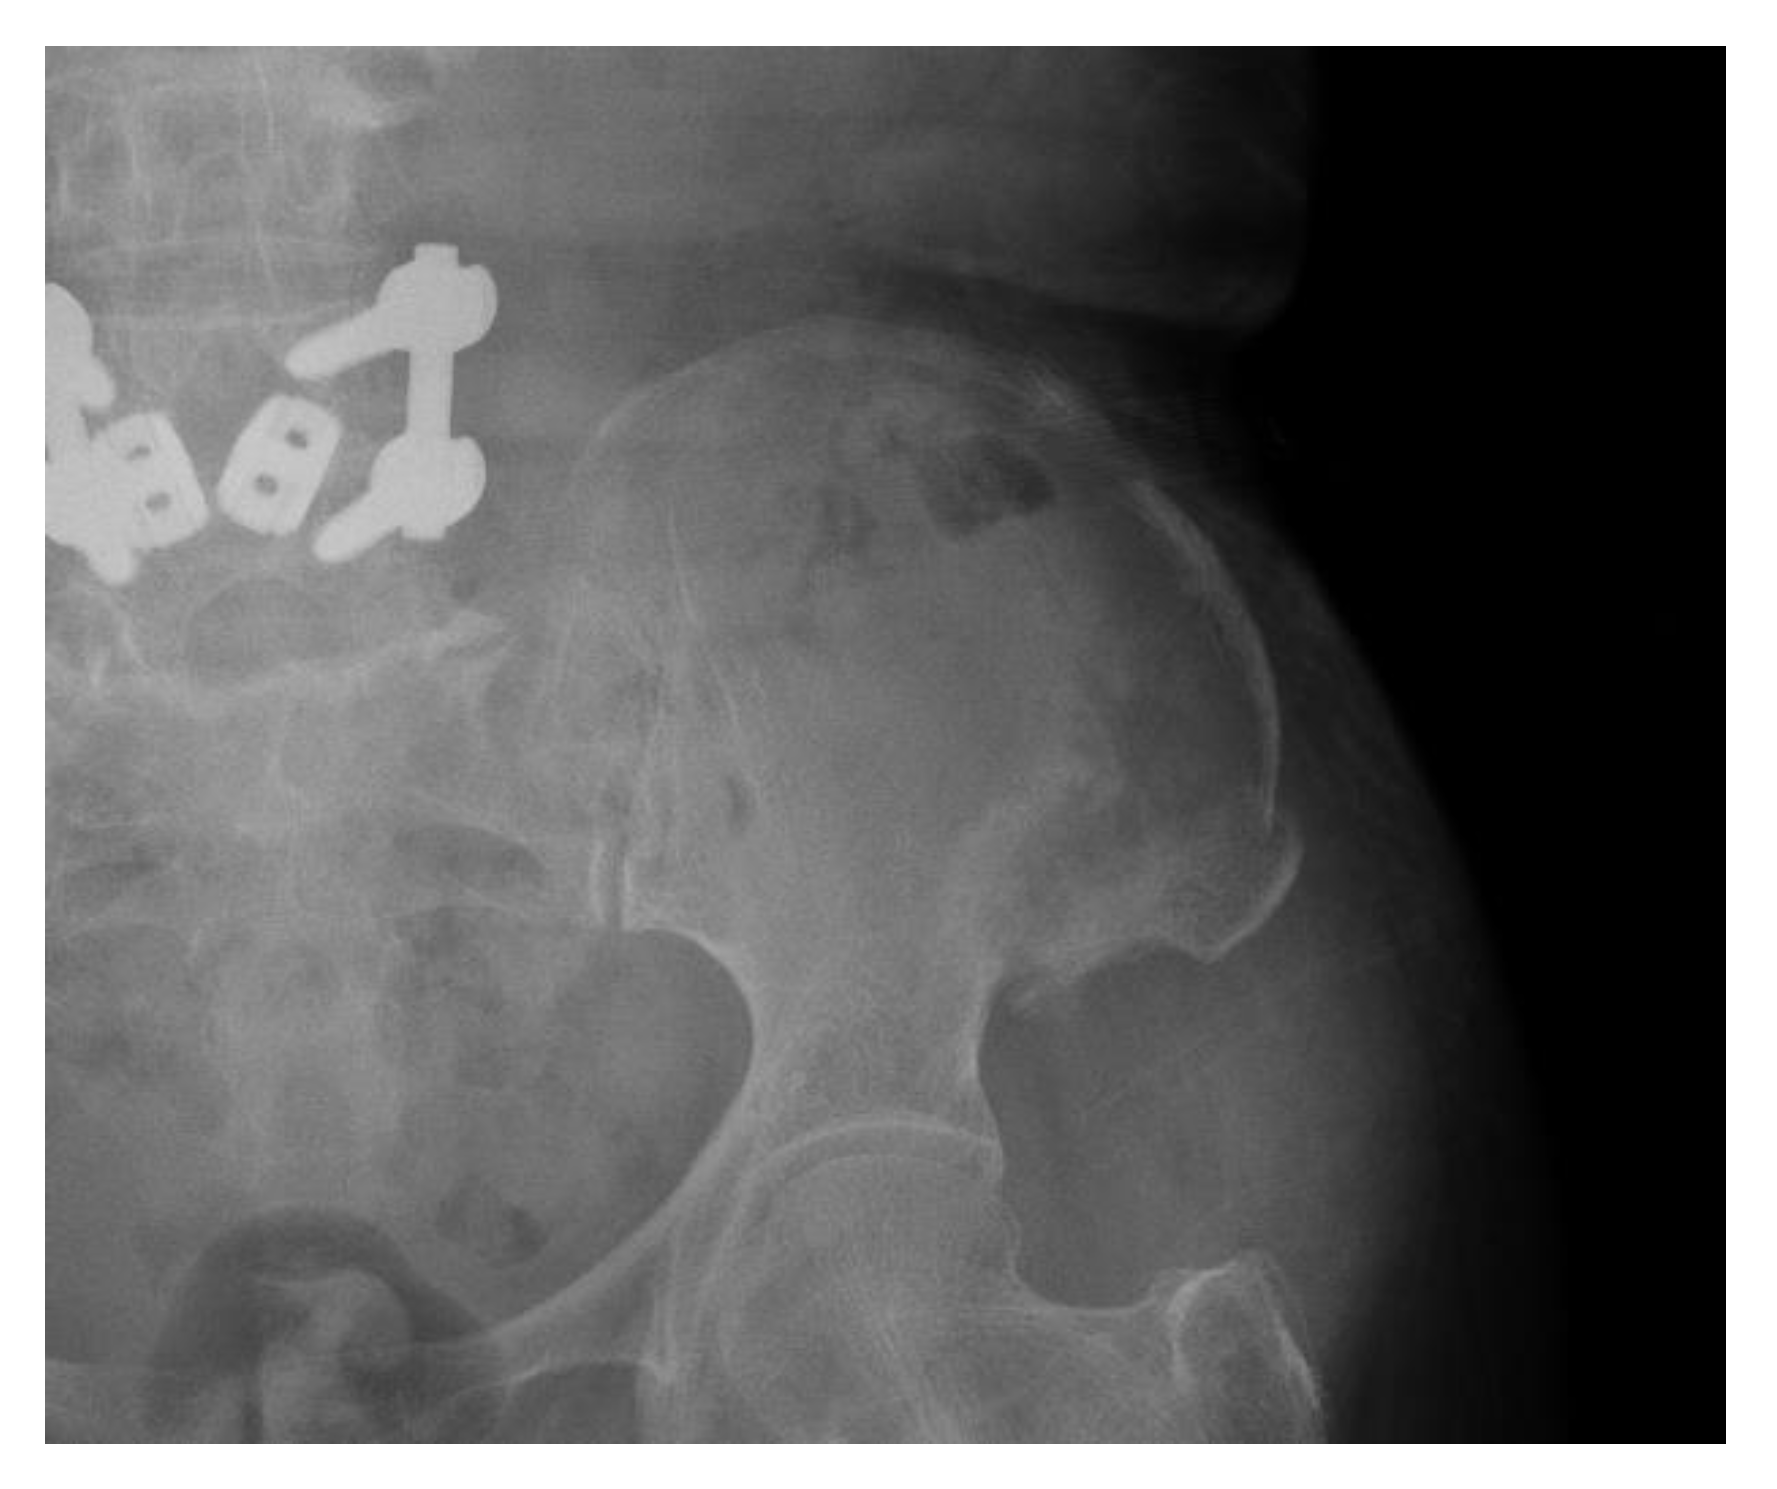

The patient complained of pain in the donor site on the 16th postoperative day when moving out of bed. A fracture line on the iliac donor site was seen on the radiograph of the iliac bone (Figure 11).

Figure 11.

Radiograph of left ilium; fracture line on iliac donor site was seen.

Conservative Treatment of Avulsion Fracture

Considering the patient’s old age and condition, the patient was managed by conservative treatment. The patient was placed on absolute bed rest for four weeks, and received symptomatic treatment and physical therapy in the department of rehabilitation medicine. One month after the fracture, callus formation was seen on a radiograph. After 4 weeks, she could walk and experienced no pain during walking practice.